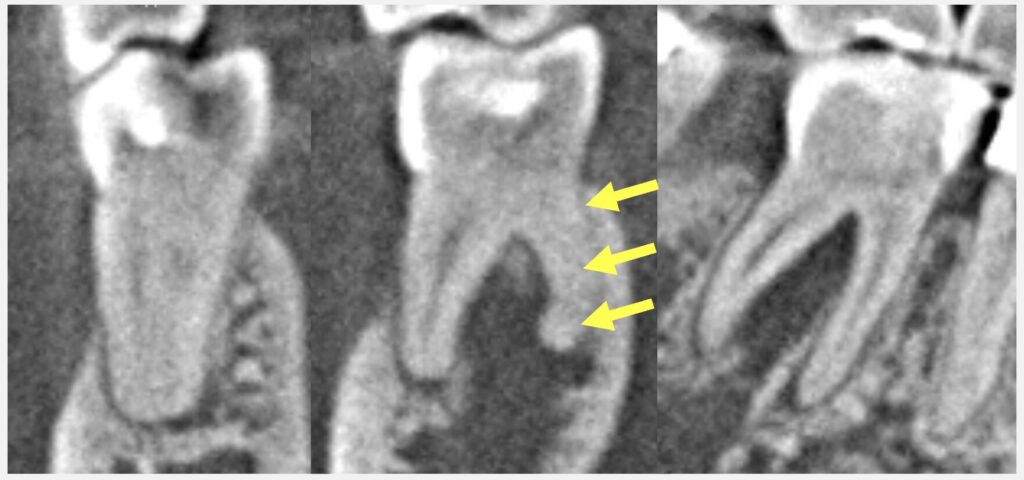

そして、CTを拝見したところ、根の周りの骨の吸収がとても大きい状態です。根の先の膿の初期は骨の中にとどまっていますが、進行すると歯茎周りの骨にまで吸収が進み、そうすると今回のように歯茎の腫れや深い歯周ポケットへとつながります。ただ、⚫️⚫️様はお口全体を見ると歯周病の傾向はあまりなさそうなので、おそらくこの深いポケットは歯周病というよりも、歯の根の問題によるものと考えられます。

今回一番問題となるのが、歯の根が強く曲がっていて、根管も狭窄して細くなっている点です。非常に珍しいというわけではありませんが、慎重に治療を進めないと、ファイル破折という治療器具が根の中で折れる可能性があります。